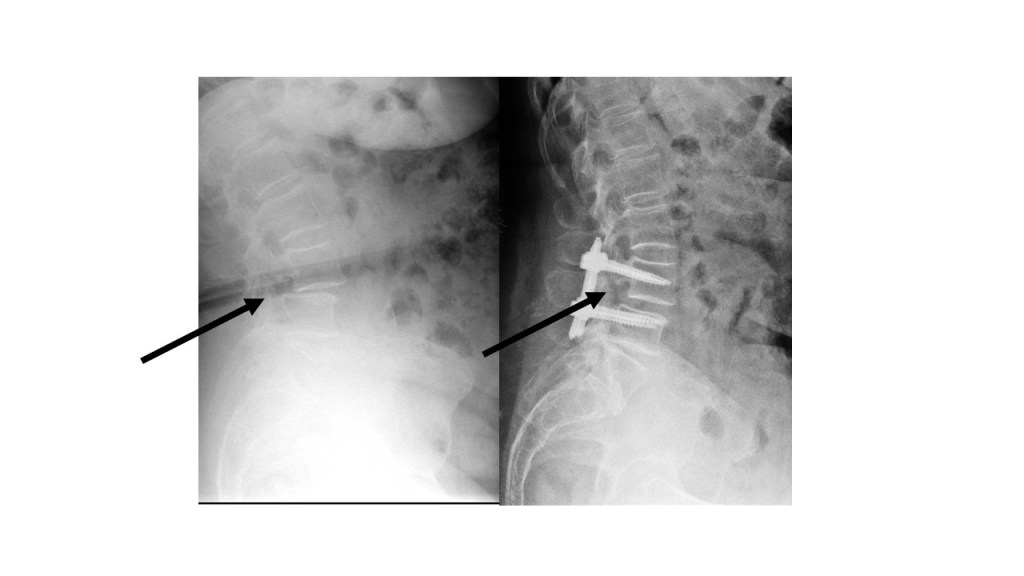

-Espondilolistesis lumbar: Por listesis entendemos el desplazamiento de una vértebra sobre otra en el plano sagital. Sus orígenes más frecuentes son el degenerativo ( propio de adultos de mediana y avanzada edad en los que la listesis suele acompañarse de un grado variable de raquiestenosis) o el espondilolítico (en adultos jóvenes y de mediana edad en los que tiene lugar la lisis o rotura de la pars interarticularis, una porción de la vértebra que interesa a la articulación intervertebral facetaria). Las listesis se clasifican en la escala de Meyerding en cinco escenarios según el grado de desplazamiento. La sintomatología de la listesis es el dolor lumbar mecánico que en ocasiones puede acompañarse de sintomatología radicular (radiculopatía) sobre todo en los casos en los que existe también estenosis de canal raquídeo. En caso de sintomatología persistente y ausencia de mejoría con medidas conservadoras, debe valorarse la intervención quirúrgica.

–Fracturas vertebrales: Frecuentes sobre todo en la columna dorso-lumbar, pueden aparecer como consecuencia de mecanismos muy diversos; desde grandes traumatismos, en cuyo caso su tratamiento puede estar condicionado por la presencia de otras lesiones, o bien tras traumatismos banales o incluso de forma espontánea, sin traumatismo alguno. Estos últimos casos definen las “fracturas patológicas” en las que es preciso buscar una causa subyacente estructural o sistémica que haya provocado el debilitamiento óseo. Esta situación es especialmente frecuente en mujeres tras la menopausia debido al desarrollo de osteoporosis. Estos casos precisan iniciar un tratamiento para compensar la desmineralizacón ósea. El tratamiento de las fracturas depende fundamentalmente del grado de deformidad asociado, la afectación de ligamentos (ambos aspectos definen la presencia o no de inestabilidad) y el que exista o no una lesión neurológica. En caso de fracturas estables sin déficit neurológico se emplea una ortesis mientras que en presencia de inestabilidad o afectación neurológica debe valorarse la cirugía.